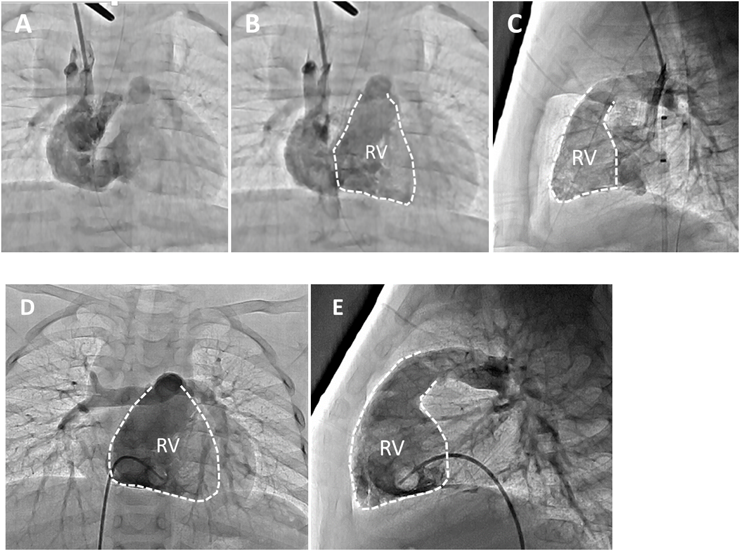

Since desaturation progressed, we performed cardiac catheterization when the patient was 3 months old. Angiography of the SVC showed that contrast media mainly flowed toward the tricuspid valve into the RV (Fig. 2A). Similar to the echocardiographic findings, the tricuspid valve’s diameter and RV volume were small (Fig. 2B, C). We performed a balloon occlusion test of the foramen ovale (FO) and compared the hemodynamic parameters and angiographic findings before and after the balloon occlusion test (Table 2). Considering the end-diastolic volume of the RV (RVEDV) and tricuspid valve’s diameter, we judged that partial closure of the FO was more preferable than total closure.

Fig. 2 Preoperative angiography of the SVC (A, B: frontal view, C: lateral view) showing that contrast media mainly flowed into the RV through the tricuspid valve. The tricuspid valve’s diameter and RV volume were small.(RVEDV 9.2 mL, 50% of normal, EF 54%,PA index 127) Postoperative angiography of the RV (D: frontal view, E: lateral view) showing that the RV volume had developed.

EF, ejection fraction; LPA, left pulmonary artery; PA, pulmonary artery; PVd, pulmonary valve diameter; RPA, right pulmonary artery; RV, right ventricle; RVEDV, right ventricular end diastolic volume; SVC, superior vena cava; TVd, tricuspid valve diameter

The patient’s room air saturation values increased and remained around 94% beginning 3 months after surgery and remained at around 95%–96% beginning 6 months after surgery; therefore, we administered home oxygen therapy 7 months after surgery (Table 3). We performed cardiac catheterization 12 months after surgery and confirmed that the RV was well-developed and had good function (Fig. 2D, E). We expected that the PFO would close spontaneously during the follow-up period.